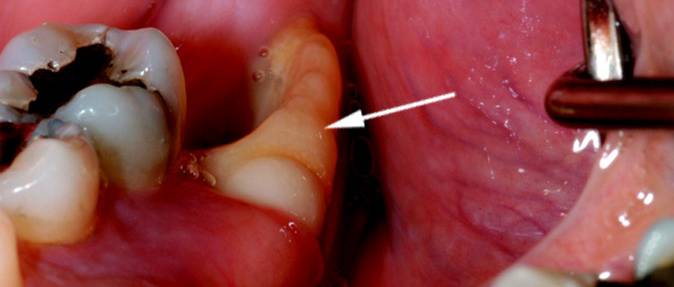

Фото

После удаления зуба многие замечают белое образование в области лунки. На форумах пользователи обсуждают свои переживания и делятся советами. Некоторые считают это естественным процессом формирования фиброзной ткани, защищающей рану. Другие же рекомендуют обратиться к стоматологу, если образование вызывает дискомфорт или не исчезает через несколько дней. Каждый организм уникален, и то, что для одного является нормой, для другого может указывать на проблему. Поэтому при возникновении сомнений лучше посетить врача, чтобы избежать осложнений.